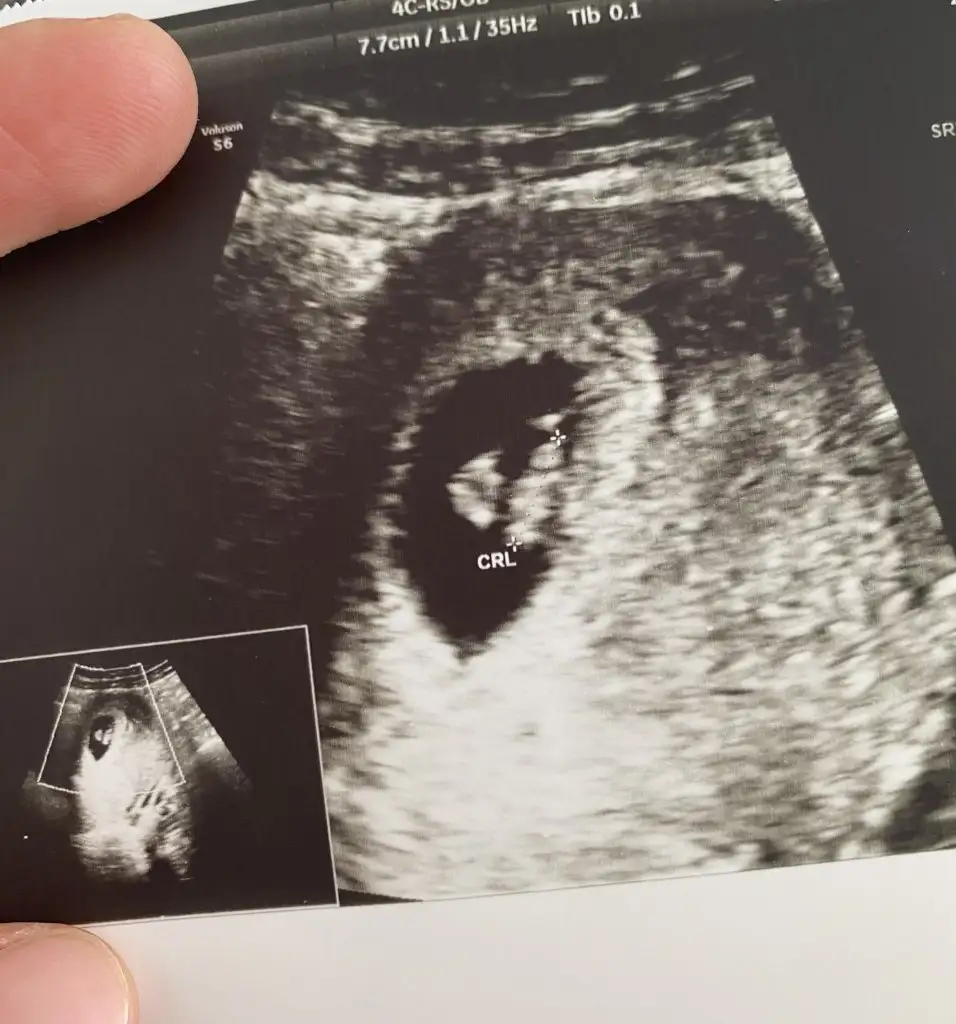

Teyzeler merhaba ilk doğum sezeryan olduğu için doktorumun 10 Ocak gibi 39+0 diye planlama öngörüsünde bulundu 7+1 olmuşuz

Eklentiler

• ED8E92B7-D160-46B9-9FD4-F6D9C5D07BDA.webp

ED8E92B7-D160-46B9-9FD4-F6D9C5D07BDA.webp

41,5 KB · Görüntüleme: 66